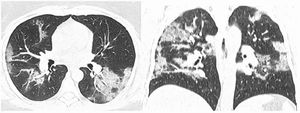

After classification, the data underwent interobserver agreement analysis, divergent interpretations were resolved by consensus. Figures 2 to 4 shows examples of our cases and the corresponding RAD-Covid Score.

RAD-Covid Score 3. Male patient, 67 years old, with 5 days of symptoms and Covid-19 infection confirmed by rt-PCR. Extensive pulmonary involvement (> 50%). In this case, we see ground-glass opacities, consolidations, septal thickening, and “crazy paving” pattern occupying more than 50% of the total lung volume, with bilateral, peripheral, and central distribution.